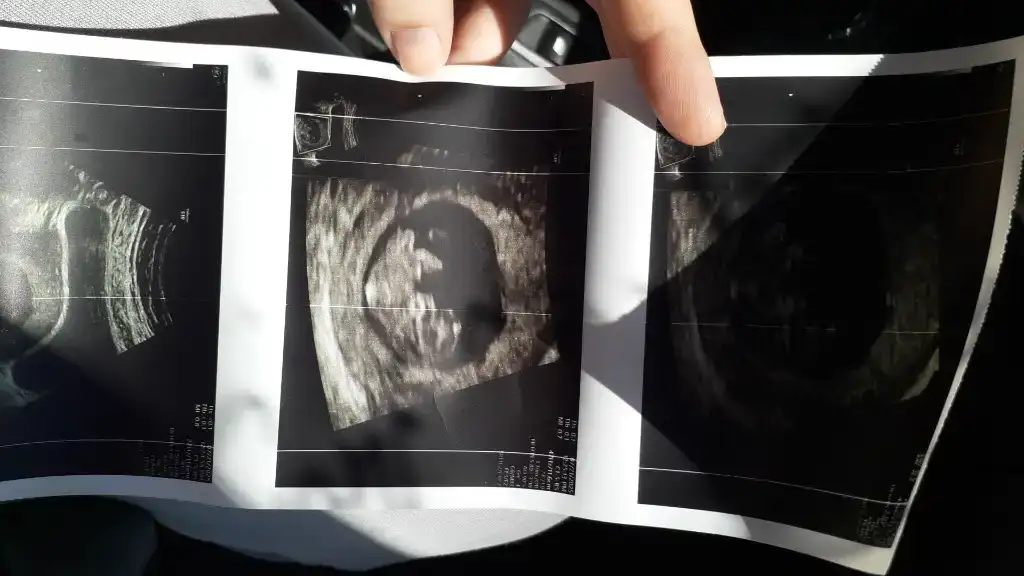

Benim nedir sizce 6+4Sizinde erkek![]()

Ben keseden anlamiyorum kese teorisine de inanmiyorum zatenBenim nedir sizce 6+4

Merak işteBen keseden anlamiyorum kese teorisine de inanmiyorum zaten![]()